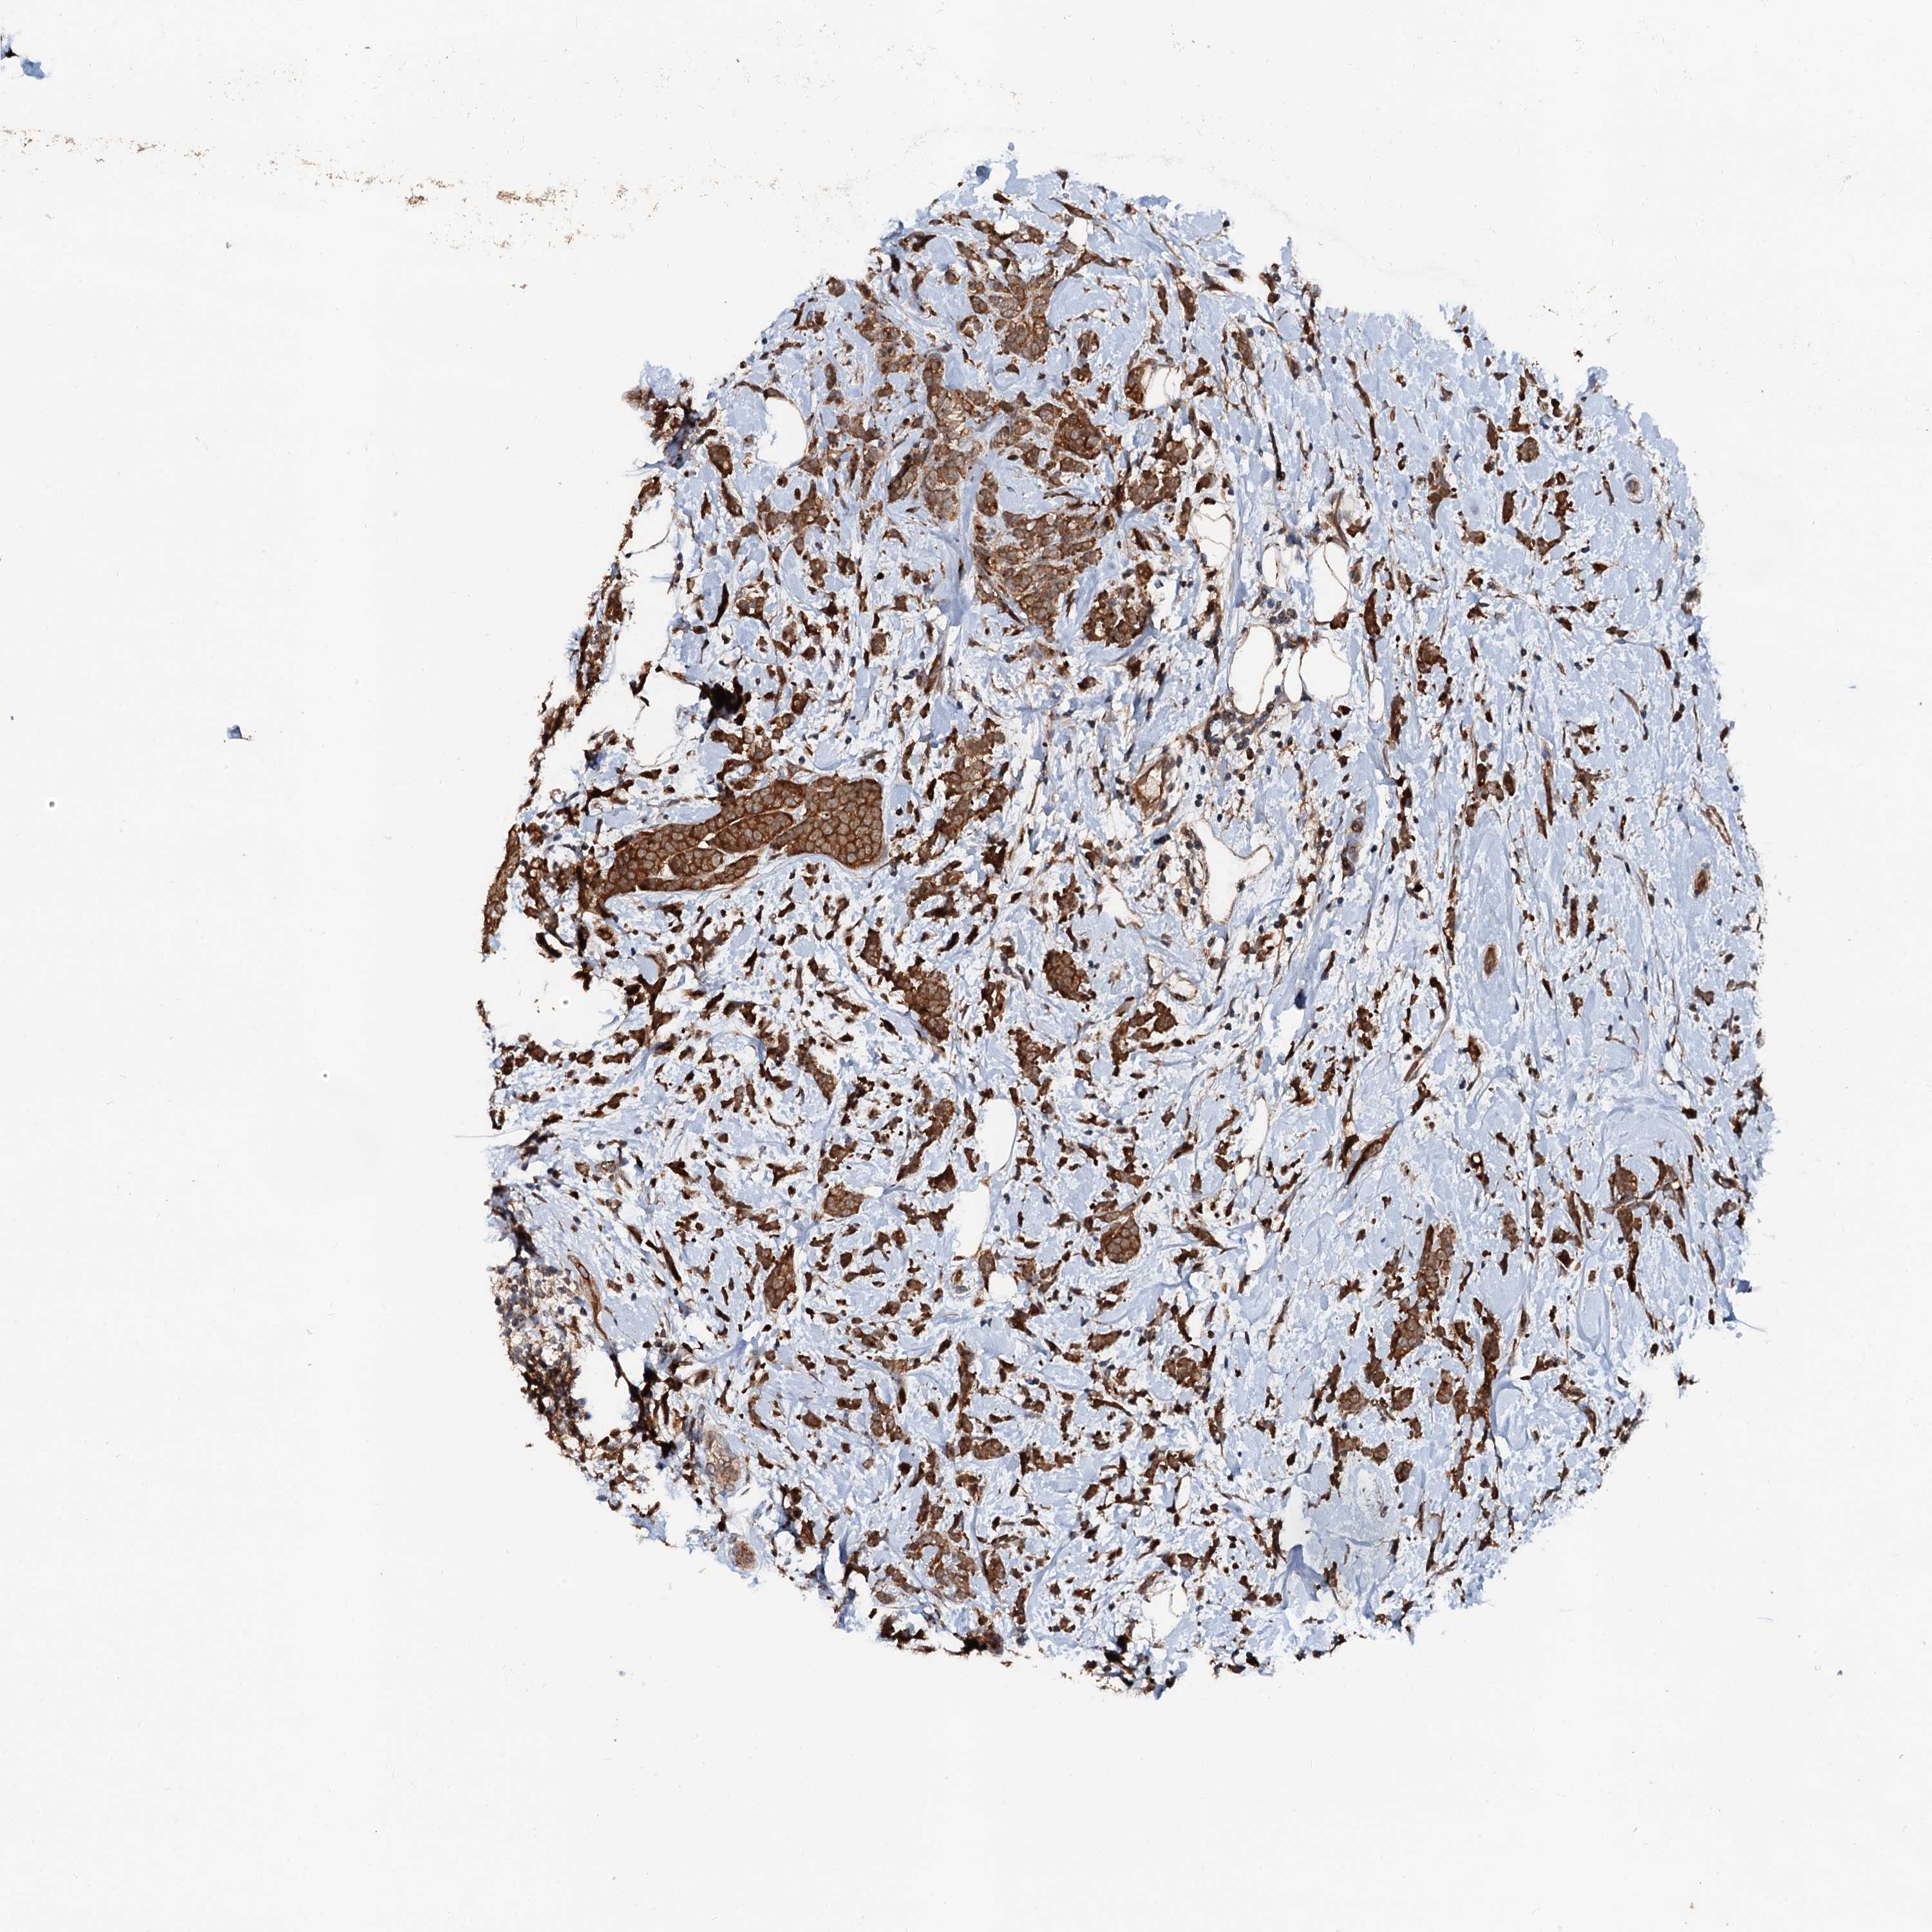

CANCER BREAST CANCER Show tissue menu

BRCA TCGA BRCA VALIDATION PROTEIN EXPRESSION